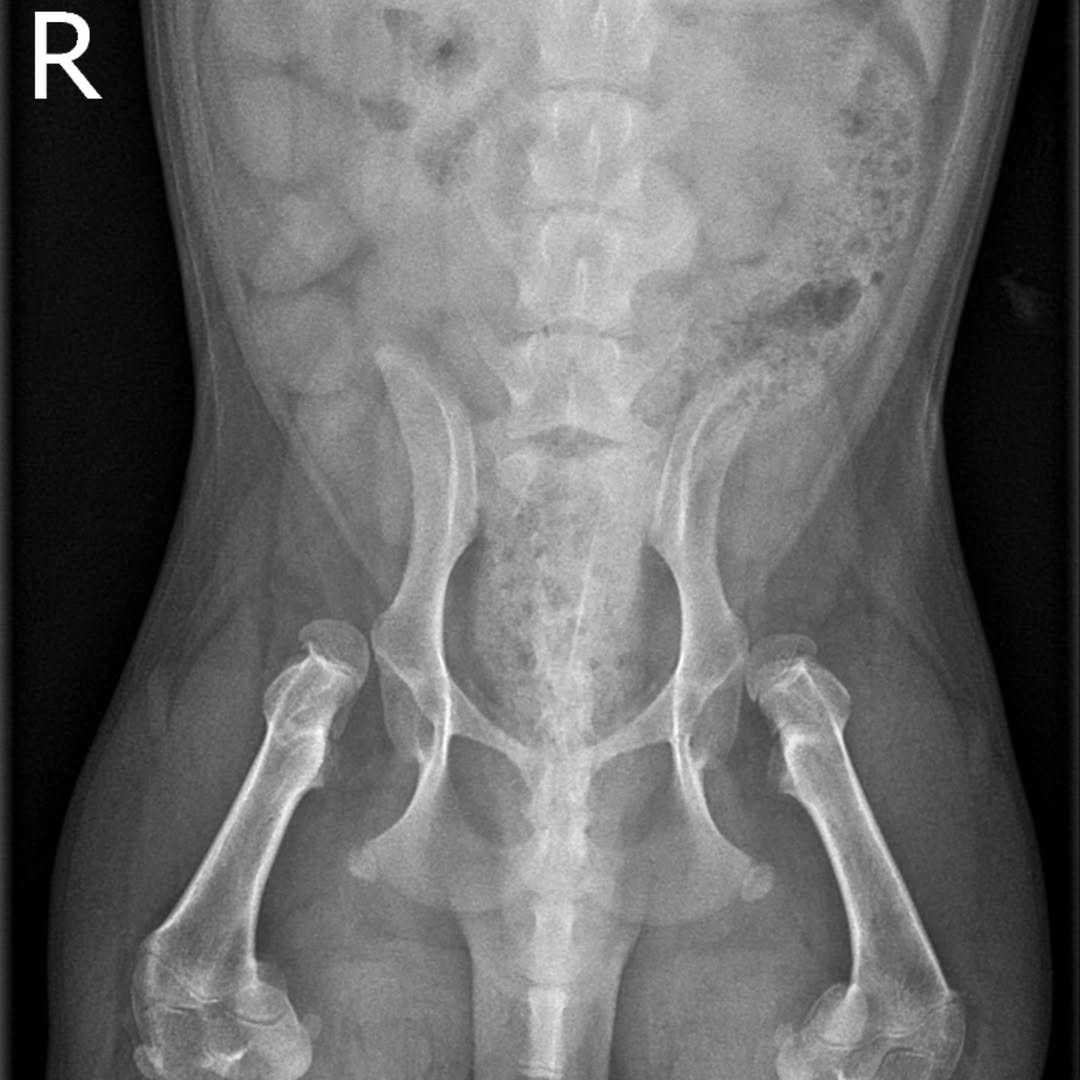

Daley was found to have hips completely out of their sockets.

According to the rescuer, this means every step he takes causes pain as the joints rub against surrounding flesh and nerves.

Daley will need corrective surgery in both hips, plus subsequent intensive hydrotherapy sessions.

He may even need a second operation, the rescuer revealed to MS News.

An X-ray of Daley’s hips. Source: @chippy.daley.dcorgis on Instagram